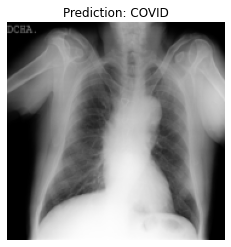

Currently, there is an urgent need for efficient tools to assess the diagnosis of COVID-19 patients. In this project, we propose a constructive solution for detecting and labeling infected tissues on CT lung images of such patients. To cut down false positives our model is trained on 4 types of lung CT images : COVID, Viral Pneumonia, Lung Opacity and normal images to get the best possible results with highest accuracy.